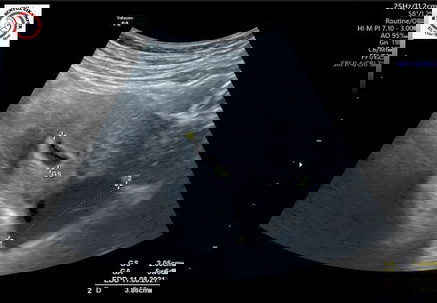

Baca lagiSaya pas usg hamil 4 week juga ada kista bun 3,7 cm. Pas pertama dengernya iya kaget sedih bgt khawatir sama bayinya tapi kata dokter jgn khawatir nanti kalo udah di atas 16 minggu usia kehamilan di cek lagi. Skrg alhamdulillah udah 31 week ga keliatan, udah ketutupan bayi. Bismillah aja bun,percaya bayinya kuat. Trus jgn terlalu di pikirin, pokoknya fokus biar bayinya sehat